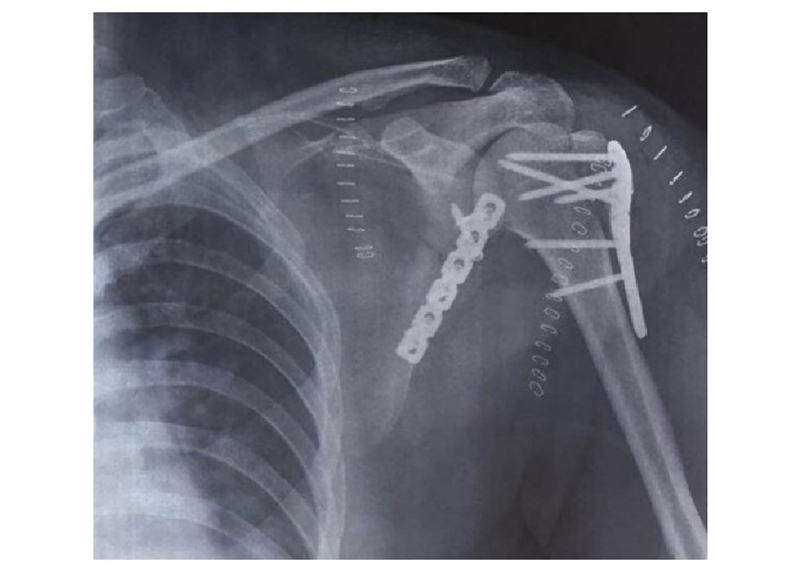

术中采用钢板固定肩胛颈内下方骨折块,肩胛骨体部骨折固定采用缝线辅助固定技术,骨折端以Nice结固定。术后CT三维重建显示骨折复位满意,固定良好(图22)。

图22 术后CT三维重建示肩胛骨骨折复位满意,内固定位置良好 图A:肩胛骨后面观;图B:肩胛骨侧面观

术后X线显示接骨板位置良好,实现肩胛骨骨折解剖复位(图25)。

图25 X线示肱骨近端及肩胛骨内固定位置良好,骨折复位满意